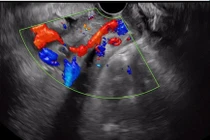

Thai phụ vào khoa Phụ sản, Bệnh viện Đa khoa trong tình trạng mắt lồi rõ, 2 chân phù, ra máu âm đạo, niêm mạc nhợt. Qua siêu âm, có 2 thai trong buồng tử cung, trong đó 1 thai sống, trọng lượng khoảng 900g và 1 thai lưu; 1 rau mặt trước bám đáy, 1 rau mặt sau, mép dưới bánh rau bám sát lỗ trong cổ tử cung.

Siêu âm cho sản phụ mang song thai bị rau tiền đạo - Ảnh BVCC